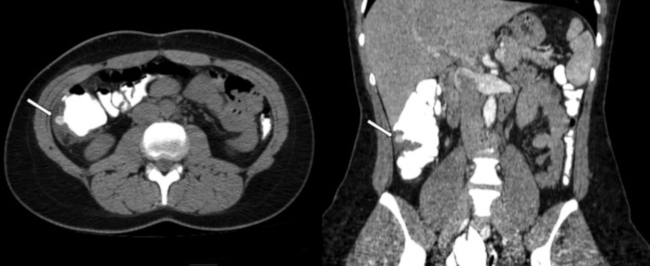

Clínicamente, dicho cuadro se caracteriza por dolor abdominal a predominio del cuadrante inferior izquierdo y fiebre, acompañado de alteración en los parámetros de laboratorio vinculables a un proceso infeccioso. En caso de complicaciones, puede progresar a un cuadro de peritonitis, presentando mal estado general, dolor a la descompresión, defensa abdominal. En ocasiones, se asocia además a hemorragia digestiva baja, estenosis post diverticulitis aguda, debiendo realizar el diagnóstico diferencial con patología neoplásica.6 Cuando la afectación compromete el colon derecho, clínicamente el cuadro es indistinguible de la apendicitis aguda, siendo los estudios por imágenes indispensables para un correcto diagnóstico (►Fig. 1).7

Estadio IA: Pequeñas burbujas de aire pericólicas o presencia de líquido libre pericólico sin absceso. Se recomienda tratamiento con antibióticos intravenosos u orales y observación hospitalaria (►Fig. 1).